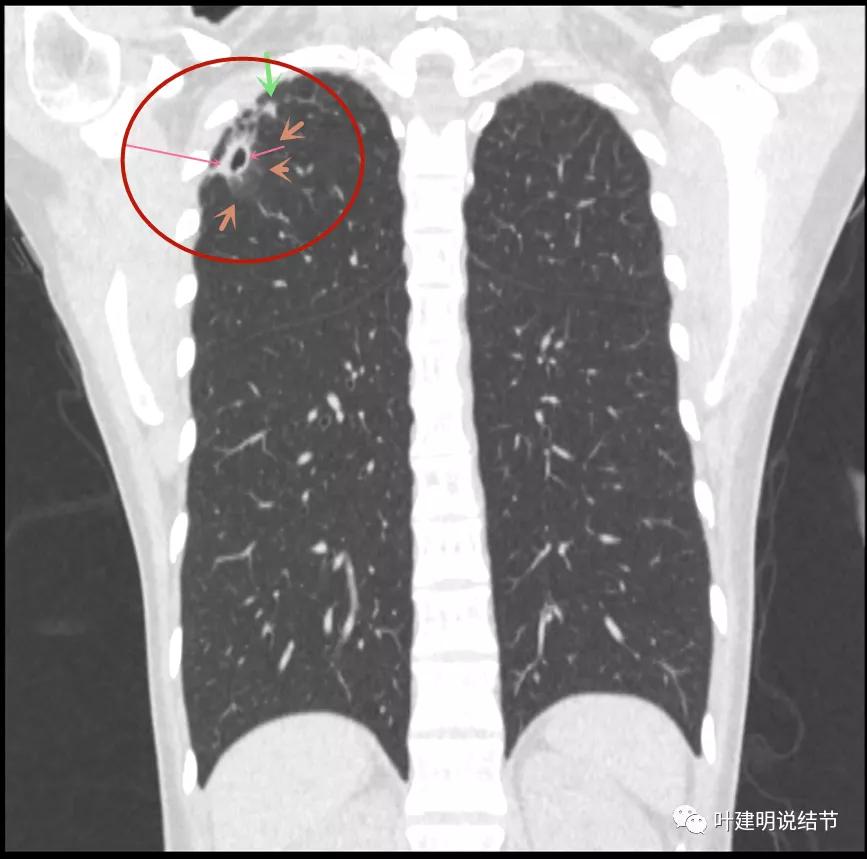

病灶较散,有磨玻璃影,但磨玻璃的边缘模糊不清(砖色箭头),囊壁密度过高(粉色箭头),毛刺样的结构偏长,空洞内壁较光滑,有卫星灶(绿色箭头)

病灶邻近胸膜增厚明显(蓝色箭头);病灶似三角形,边缘平直(桔色箭头);有磨玻璃淡且散,边缘不清(砖色箭头);有卫星病灶(绿色箭头)

病灶与胸壁间不似毛刺,像炎性粘连(相连的结构粗细均匀,没有离开病灶后变细,密度较高,邻近胸膜也增厚的);有卫星状(绿色箭头);有淡且散的边缘不清的磨玻璃成分(砖色箭头)